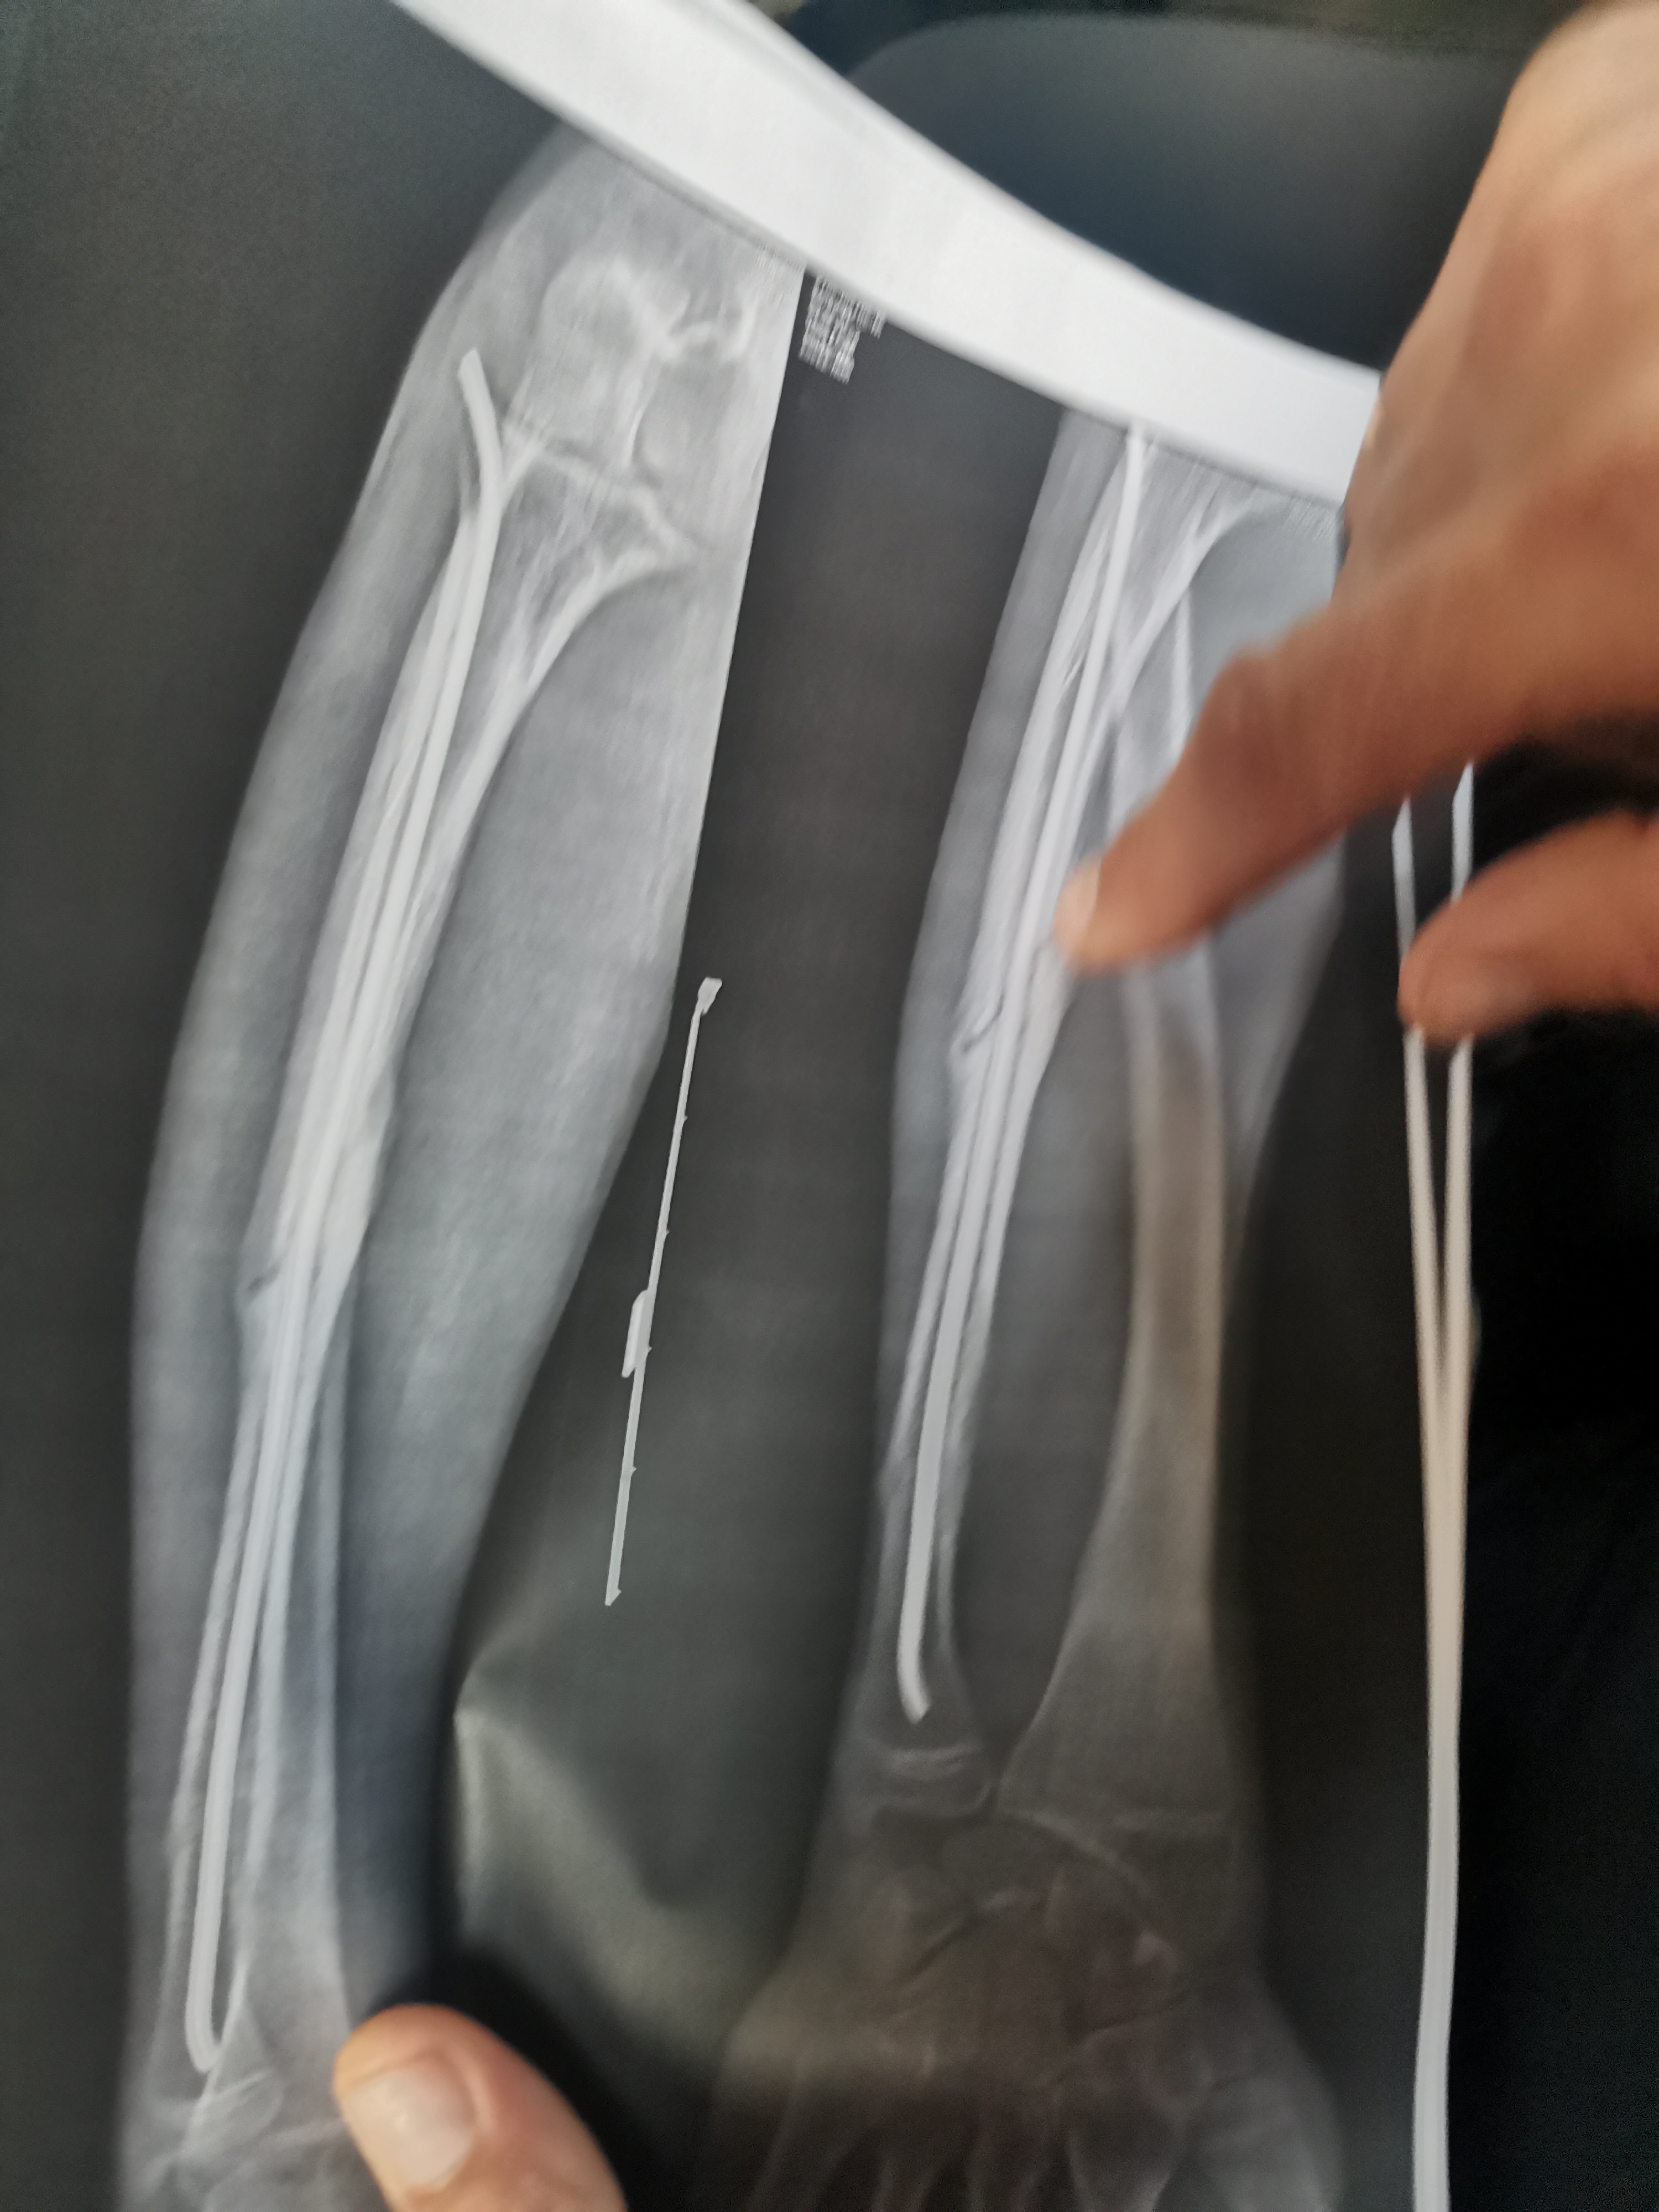

Перелом ключицы Аноним 20/03/26 Птн 00:46:30 1662761 Ответ

IMG202603092132[...].jpg 1684Кб, 2080x4624

2080x4624

Всем привет

У меня сломана ключица на правой стороне. Перелом со смещением, есть 5 болтов. Тяжело поднимать тяжести, начинает ныть рука.

Могут ли призвать в армию в 2026? У меня будет повторная медкомиссия. Будут скорее всего давить на то, чтобы я как-то снял пластину